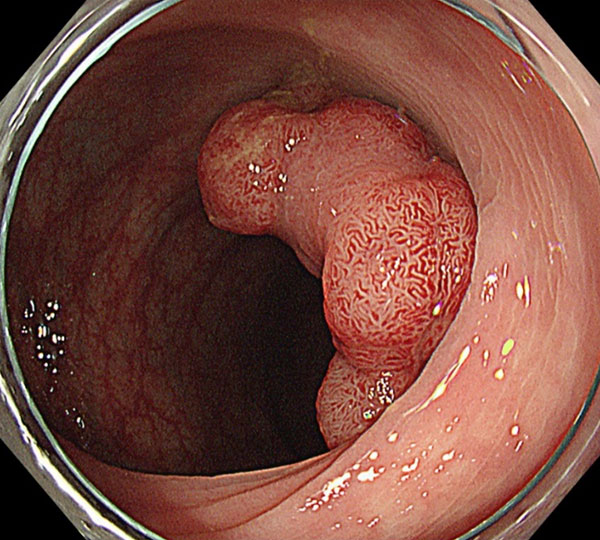

2. 4cm大の早期大腸癌(粘膜内癌)です。

3. 病変の肛門側から粘膜切開を開始します。切開は内視鏡先端が入れる程度の大きさにとどめます。

4. 粘膜切開縁から粘膜下層の剥離を開始します。